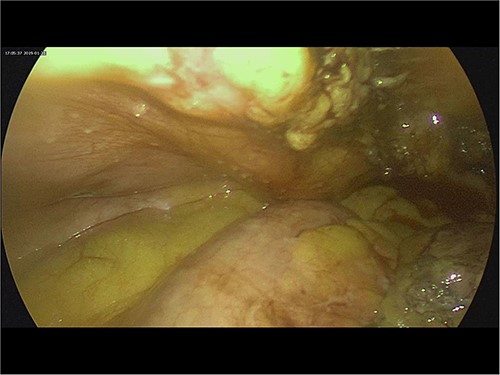

Intra-operatively, adhesiolysis of dense bowel and omental adhesions were performed. About 3.5-cm appendicular stump was resected (Fig. 3). Micro-nodular peritoneal nodules were noted and resected (Fig. 4). The specimens were sent for a histo-pathology examination. The postoperative period was uneventful with symptomatic relief. The biopsy of the gross specimen of stump appendix described a single white to grey brown soft tissue measuring 3 cm × 2 cm × 0.8 cm with a congested outer surface. The appendicular wall was 0.3 cm thick while the peritoneal nodule was a 2.5 cm × 0.8 cm × 0.5 cm single grey white to yellow soft tissue. Microscopic report of the appendix revealed multiple granuloma composed of epithelioid cells, macrophages, lymphocytes and multinucleated giant cells (Fig. 5). Caseation necrosis was seen in focal areas and with transmural mixed inflammatory cell infiltrate (Fig. 6). The peritoneal nodule showed fatty tissue with infiltration of lymphocytes, plasma cells and neutrophils microscopically.